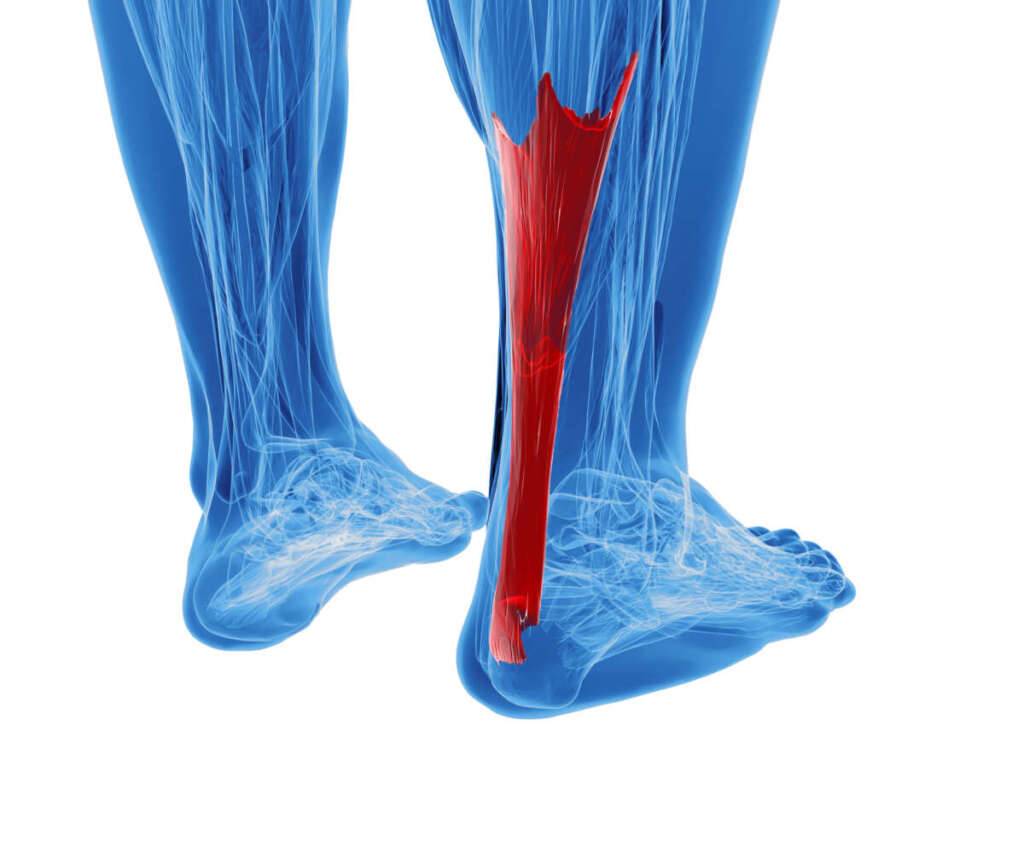

Tendinopathie Achillessehne

Die Achillessehne ist eine der stärksten und längsten Sehnen des Körpers. Die Achillessehnen-Tendinopathie bezeichnet eine Schädigung der Sehne, die die Wadenmuskeln mit dem Fersenbein verbindet. Sie äußert sich durch Schmerzen in der Vorderseite oder im vorderen Teil des Knies und Steifheit und ist bei körperlich sehr aktiven Menschen recht häufig. Zügiges Springen und Langstreckenläufe, bei denen die Sehne wiederholt beansprucht wird, tragen zur Entwicklung einer Achillessehnenerkrankung bei.